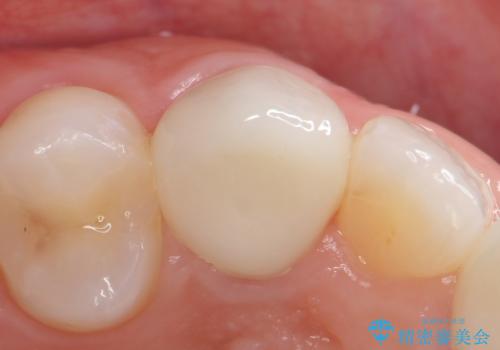

再根管治療終了後、オールセラミッククラウンによる補綴を行いました。

前歯の補綴ではオールセラミッククラウンを希望される患者様が多いですが、オールセラミッククラウンの中でも、エコノミー、スタンダード、スペシャル、エクセレントとランクがあります。

その中でも特に審美性が高いのがスペシャル、エクセレントです。スペシャル、エクセレントは口腔内写真をもとに熟練の技工士が、患者様の口腔内に合わせたオーダーメイドのクラウンを製作致します。